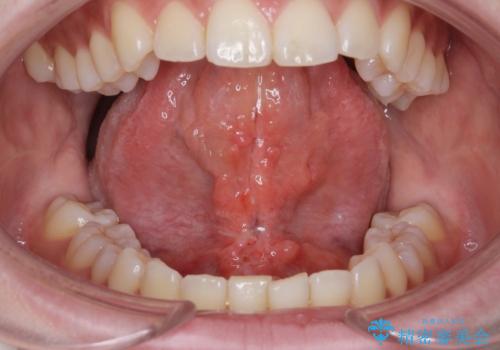

舌小帯切除

- ら行が言いにくいとの事で来院。舌の動きを舌小帯が邪魔していたので舌小帯の形成術を行いました。

舌小帯の形成手術を行うことにより舌が口蓋に届くようになり

ら行が言いやすくなりました。

舌小帯の手術は当日行うことができます。